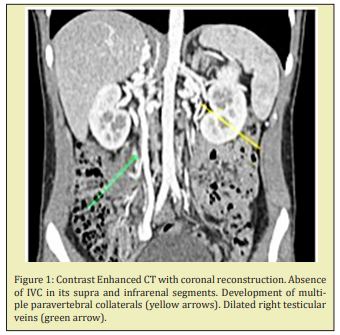

16-year-old male with no previous morbidity in his clinical records, arrived at the Emergency Room seeking treatment for a two-week long case of pain and swelling in his lower right extremity, with no other associated symptomology. The patient had no smoking habit, had not undergone prior surgeries, had not traveled long distances, nor had he suffered trauma within the prior 30 days. In the physical exam, the increase in volume of the lower right extremity was noted and a positive Homan’s sign. The rest of the physical exam produced no other pathological findings. Due to suspicion of a deep vein thrombosis a Venous Doppler ultrasound was performed, which confirmed the diagnosis of a femoral-popliteal DVT. As part of the etiopathogenic study, a contrast-enhanced ultrasound of the pelvis and abdomen was done, on which the agenesis of the suprarenal inferior vena cava was identified, as well as multiple resulting collaterals (Figure 1). Negative thrombophilia study. An echocardiogram was taken to complete the check for associated malformations, with no pathological findings. The decision was made to treat the patient with graduated compression stockings associated to low-molecular weight heparin, with later overlap to vitamin K antagonists and the indefinite extension of the treatment. There was a good clinical response, with a gradual decrease of the edema. In the 18-month follow-up, the patient remains asymptomatic. There have been no new episodes of DVT, nor signs of post-thrombotic syndrome.